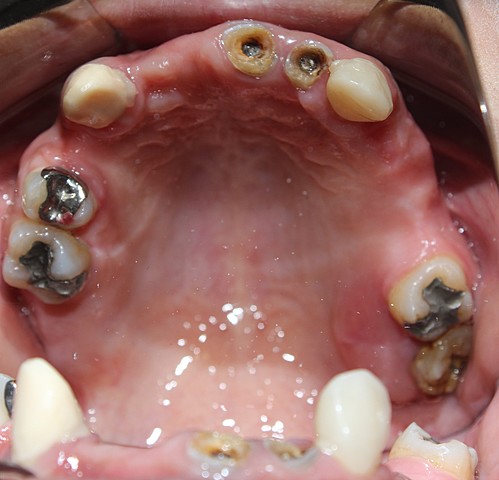

• FOTOS INTRAORALES

FOTOS INTRAORALES

Se realiza toma fotografica intraoral, donde se registra que el paciente se encuentra parcialmente edentulo tanto en carcada superior como inferior.

• DIAGNOSTICO

DIAGNOSTICO

El paciente ´resenta edentulismo parcial en ambas arcadas poe ausencia de OD. 1.1, 1.2, 1.4., 1.7, 1.8, 2.4, 2.5, 2.6, 3.7, 3.8, y 4.6.

amalgamas filtradas en OD.1.6,2.6,3.4,3.5,4.8.

Endodoncias previamente en OD. 2.1 y 2.2, lesiones apicales en OD. 1.3, 1.6, 2.3, 3.5, 3.6 y 4.1

curacion provisional de HC: filtrada en OD. 3.7. remanente radicular 4.5